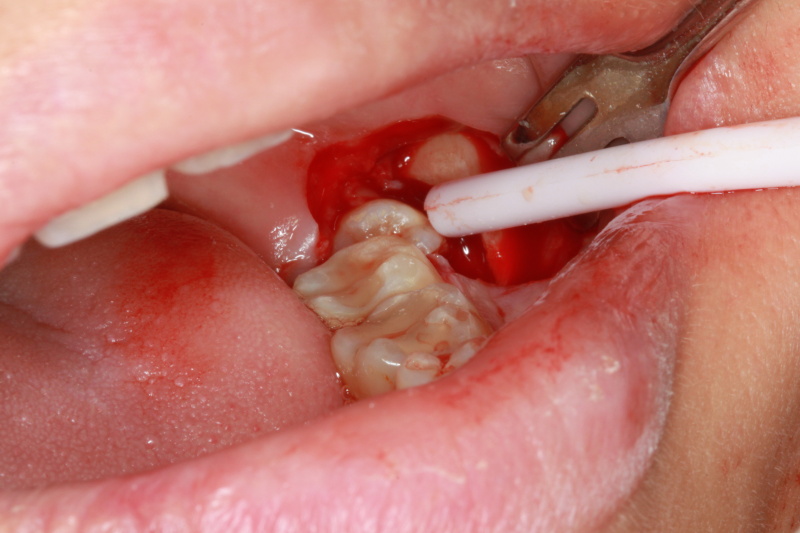

Fig 3 : Incision made to expose the wisdom tooth

Fig 4 : Impacted wisdom tooth exposed